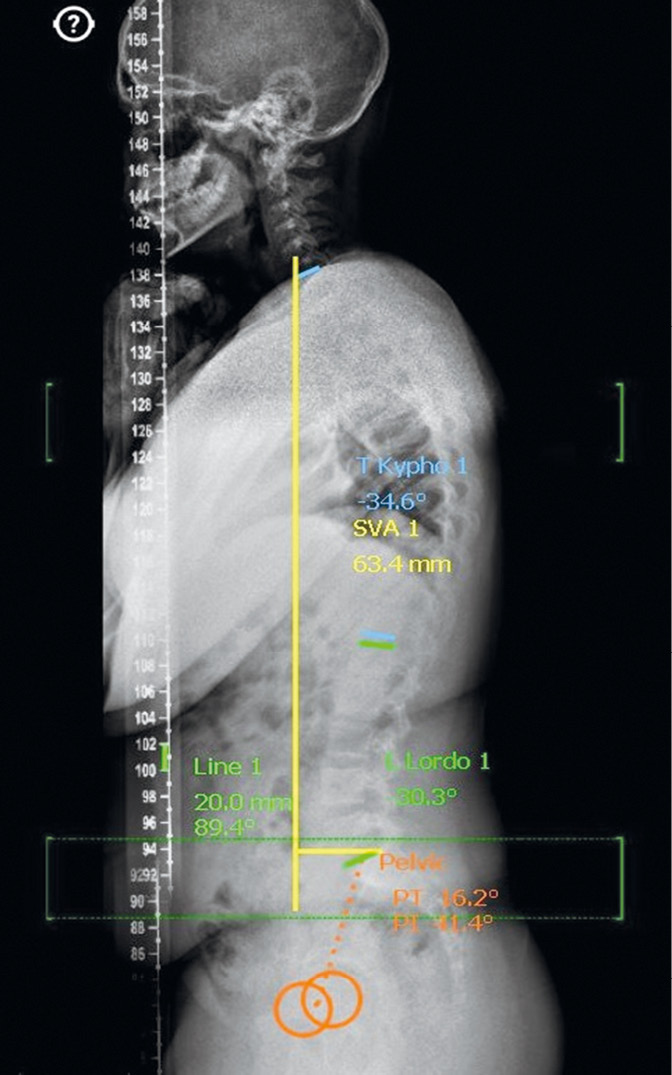

The clinical study did not differ from the classical technique used in patients with orthopedic pathology of the hip joints. All patients underwent radiography of the hip joints in the anteroposterior projection and Lauenstein projection in the supine position, a panoramic radiograph of the lower extremities, and a lateral panoramic radiograph of the spine, including the femoral heads in the standing position. On radiographs taken in the supine position (Fig. 1), the values of the projection caput–collum–diaphyseal angle, projection epiphyseal–diaphyseal angle, and epiphyseal angle were determined, and signs of partial, and complete synostosis at the level of the epiphyseal growth zone were excluded. In addition, the posterior and downward epiphyseal displacement angles were evaluated on the displacement side, and the absence of the epiphyseal displacement was confirmed on the contralateral side. The posterior epiphyseal displacement angle was calculated from the difference in the epiphyseal angles in the joint without (individual norm) and with displacement. The downward displacement angle was calculated by the difference between the caput–collum–diaphyseal angle and the epiphyseal–diaphyseal angle in the joint with displacement. On radiographs taken in the standing position (Fig. 2), indicators of the magnitude of thoracic kyphosis and lumbar lordosis (according to Cobb), pelvic incidence (PI), sacral slope (SS), pelvic tilt (PT), sagittal vertical axis (SVA), and spinosacral angle (SSA) were determined.

Fig. 2. Lateral panoramic radiograph of the spine, including the femoral heads of the same patient, and an example of the calculation of spinopelvic ratios

The coefficient of determination (R2) for the relationship of some indicators of the sagittal spinopelvic ratios and the extent of the posterior epiphyseal displacement (Fig. 4a, b) did not exceed 0.66 and did not differ significantly between the linear and quadratic models, which brought the studied signs closer to linear regression, and the approximation was considered quite good because 65% of the sample can be justified by the regression equation. The coefficient of determination (R2) between SS and GLL was 0.51 and that between SS and SSA was 0.6. Both models did not differ significantly from each other, and the approximation was considered satisfactory because no more than 60% of the sample can be justified by the regression equation. Thus, based on the regression analysis in pediatric patients with severe SCFE, a hypolordotic type of vertical posture is formed according to the classification of P. Roussouly. In addition, the formation of hyperkyphosis and a pronounced anterior shift of the SVA can be regarded as a mechanism for compensating the balance of the body in the case of pelvic retroversion and flattening of the lumbar lordosis to maintain the ability to move in a vertical position.